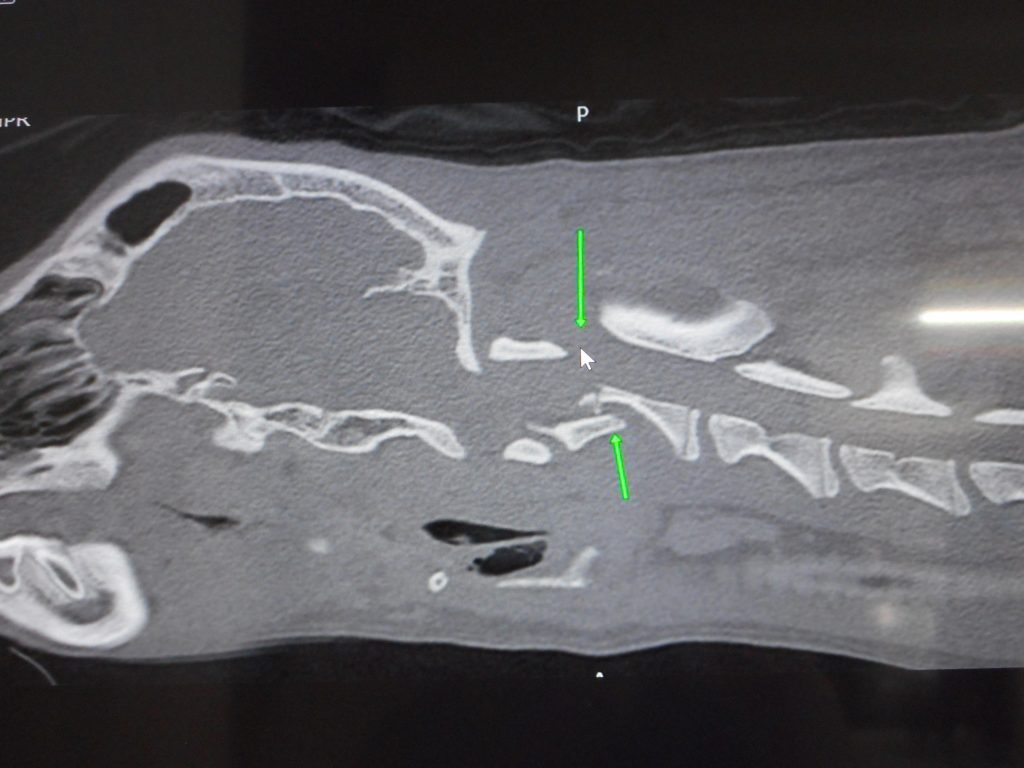

診断:第二頸椎椎体骨折および頸髄の圧迫の疑い

厳しい戦いになりそうですが、呼吸は安定しています

A fracture of the second cervical vertebra was diagnosed by CT scan.

A tough battle has begun.